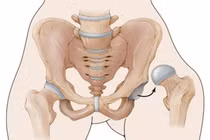

SuperPath là một trong kỹ thuật thay khớp háng tiên tiến nhất hiện nay. Phương pháp này được chỉ định phẫu thuật rộng rãi các bệnh lý khớp háng khác nhau như: hoại tử chỏm xương đùi, thoái hóa khớp háng, gãy cổ xương đùi...

Thay khớp háng ít xâm lấn có vết mổ nhỏ hơn, thẩm mỹ hơn, và phục hồi sau mổ nhanh hơn. Tuy nhiên để thực hiện kỹ thuật này phẫu thuật viên và e kíp mổ phải có kinh nghiệm và có đủ dụng cụ phẫu thuật chuyên dụng.